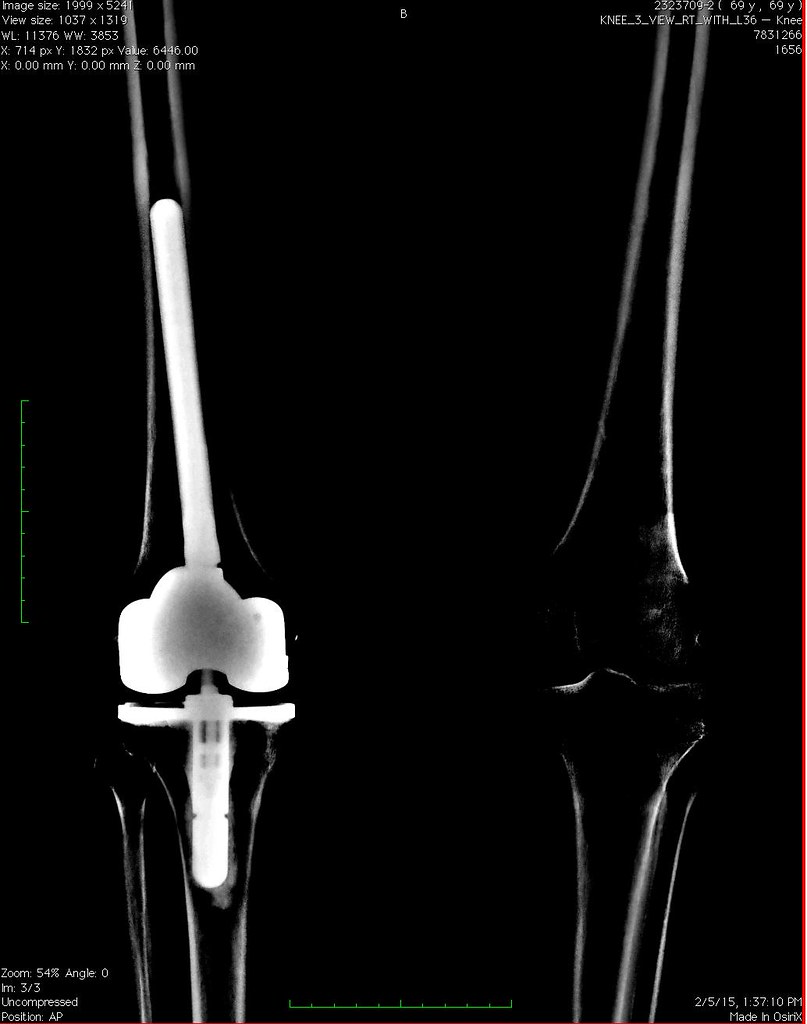

TKR (Total Knee Replacement a Zimmer model LCCK) both legs… Flickr Zimmer Knee Xray Zimmer biomet's edge and mobile health compatibility. Stryker may argue that ct scans offer greater accuracy, whereas zimmer biomet emphasizes the cost and time efficiency of their approach. Rosa knee supports surgeons in performing total knee arthroplasty (tka) with features to assist with bone resections and assessment of soft. Rosa knee system before surgeries. The following video demonstrates the surgical. Zimmer Knee Xray.